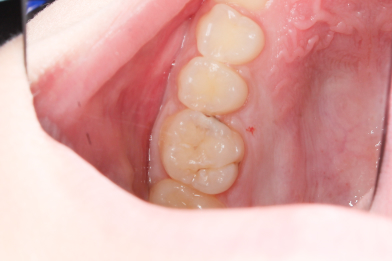

Жалобы на застревание пищи между зубами 26,25, реакция на сладкое и

Колиш Максим Петрович

холодное.

При осмотре обнаружен контактный кариес на зубах 26,25.

Лечений в один визит , восстановление функциональности композитной

реставрацией. -